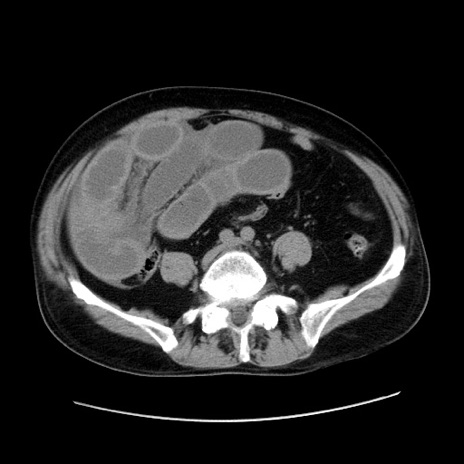

冠状断像

【症例】80歳代男性

【現病歴】約6時間前から臍下部痛が出現。次第に腹部膨隆・背部痛も生じてきたため来院。背部痛の場所は変化しない。

【身体所見】意識清明、BT 36.3℃、BP  131/87mmHg、P 87bpm、SpO2 100%(RA)、臍周囲自発痛・圧痛あり、反跳痛なし、自発痛部位に一致して板状硬あり、腹部膨隆、腸雑音減弱、CVA tenderness両側陰性。

【データ】WBC 19600、CRP 0.33